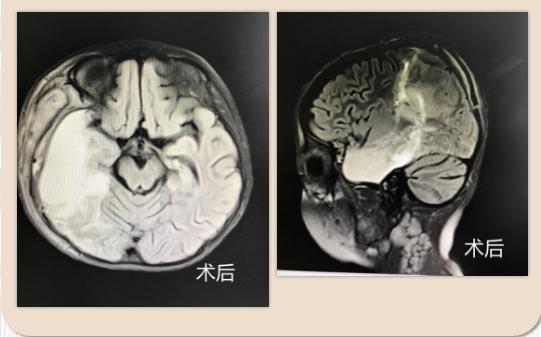

通过与北京首都儿研所团队进行多学科讨论后决定行“右侧颞叶切除,颞顶叶离断术”。手术顺利结束后,目前小蕊已转回普通病房,一天数十次的发作神奇般的消失了。